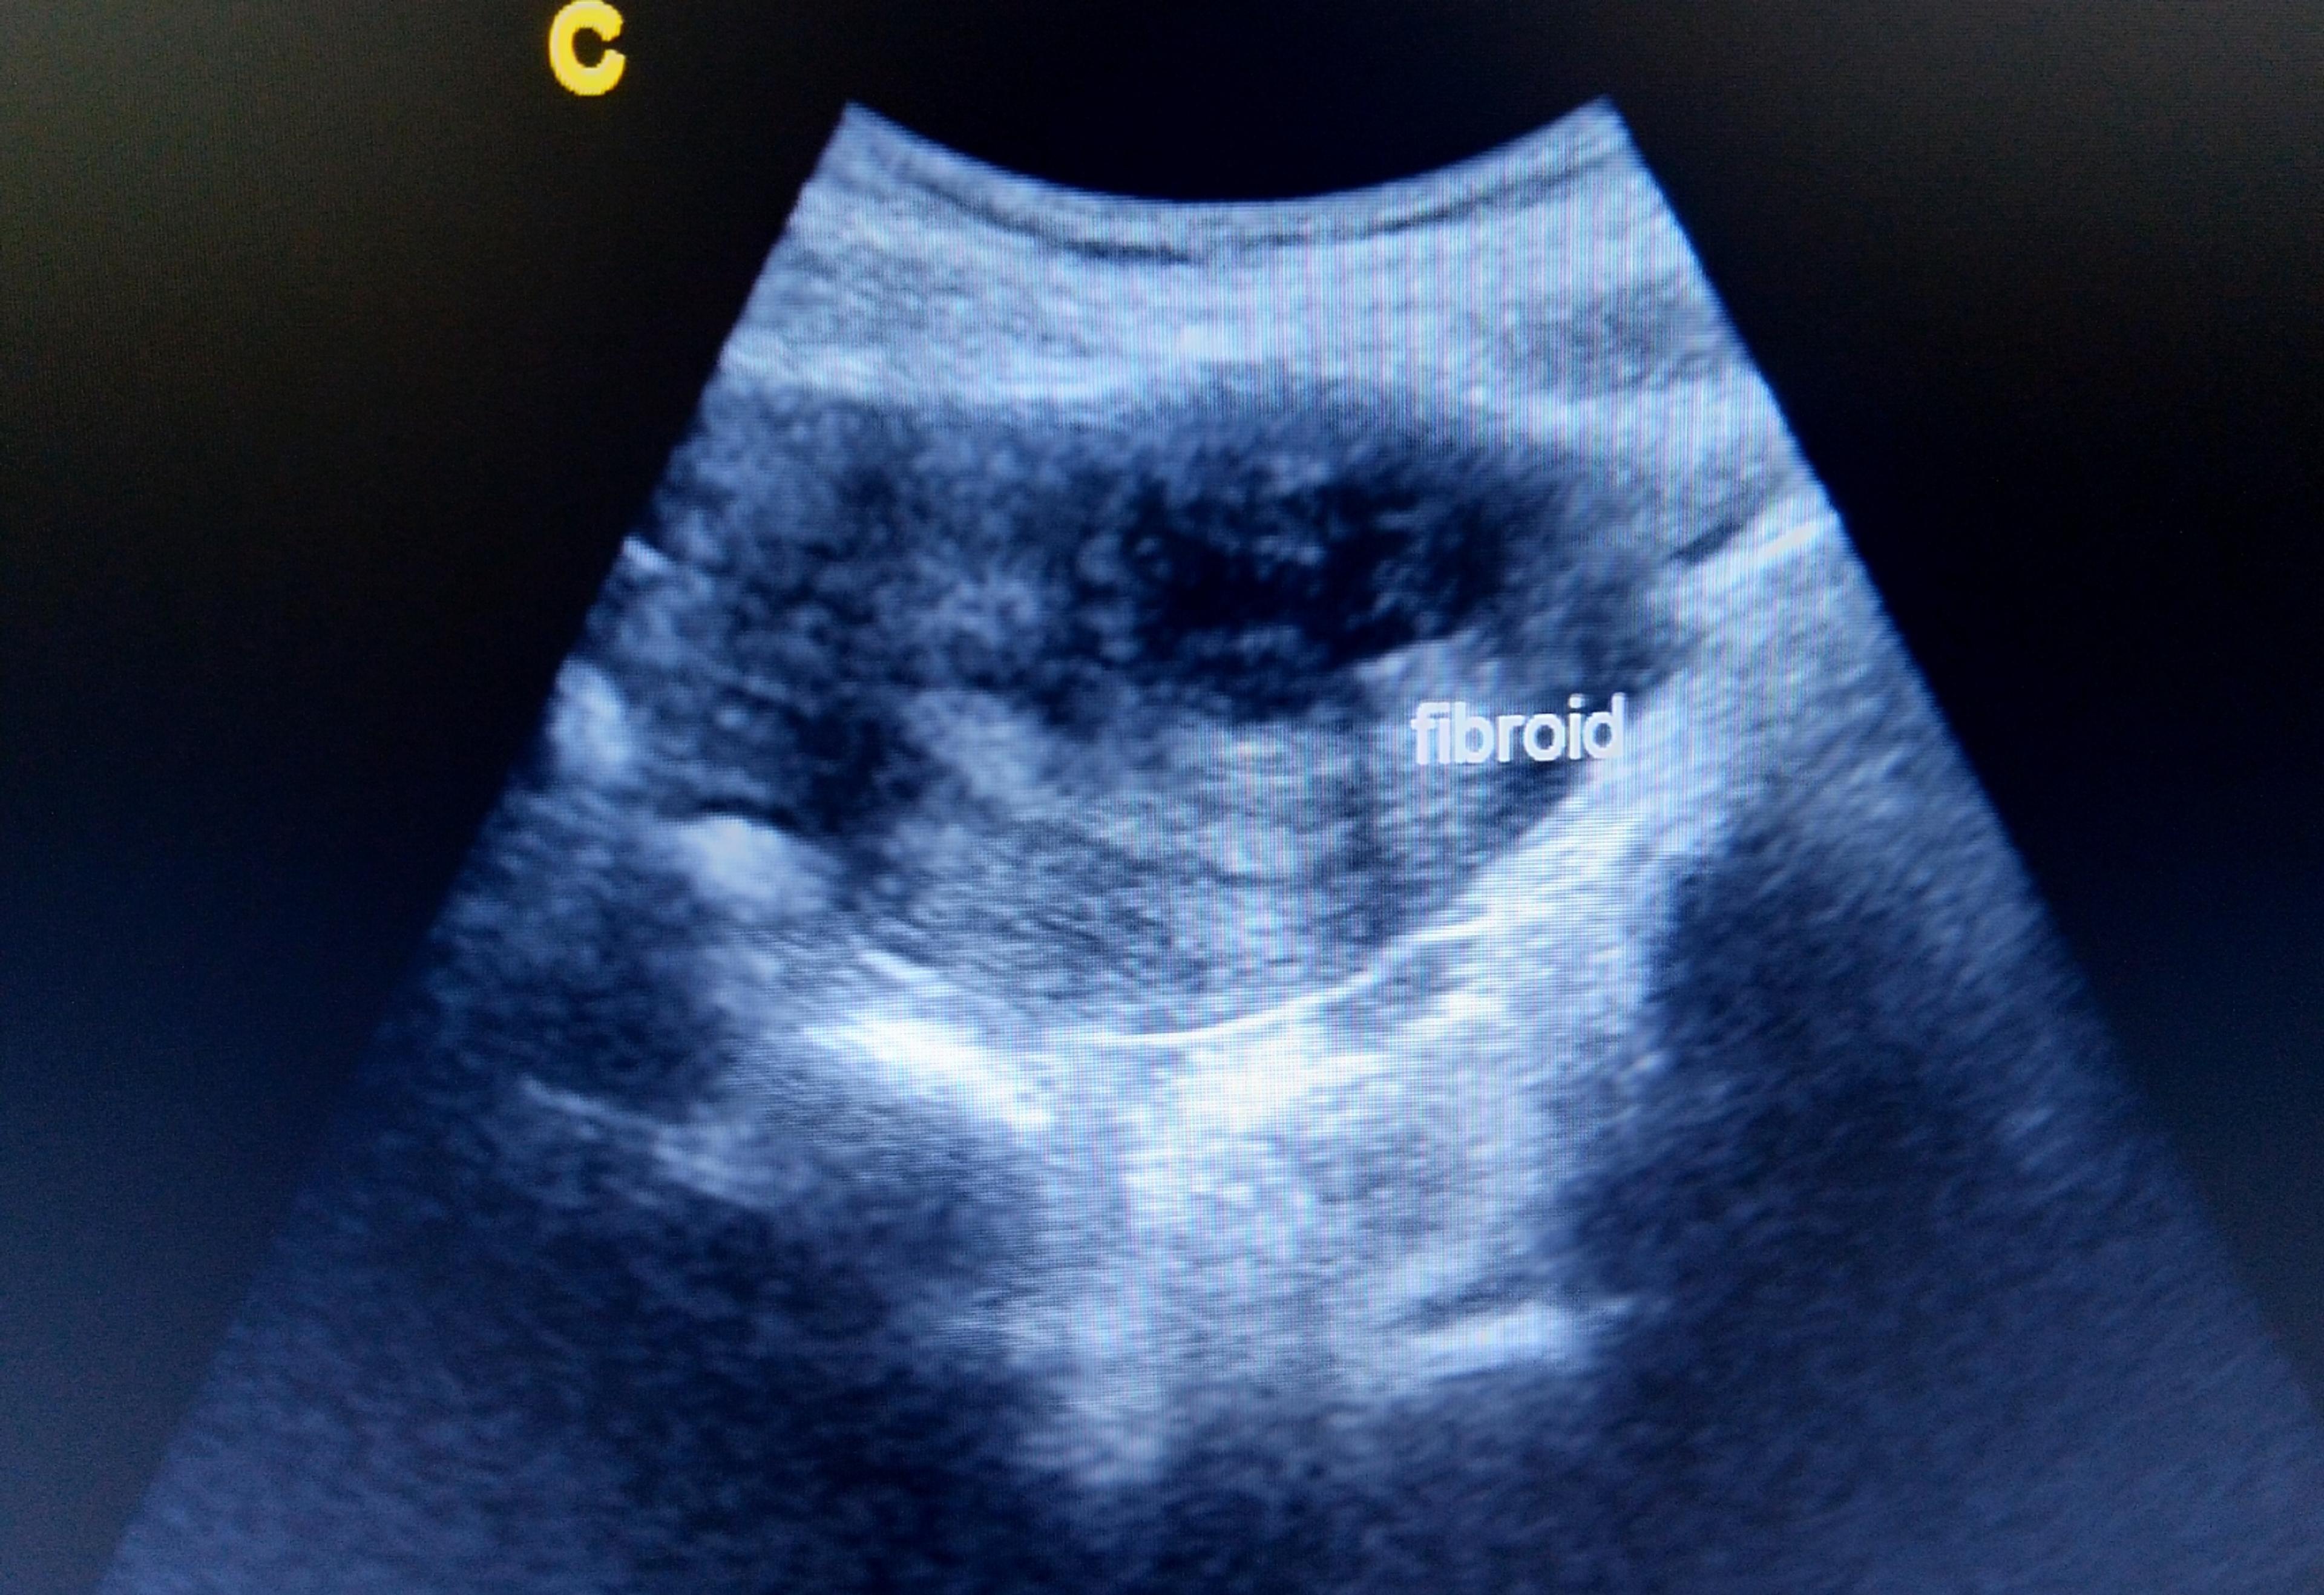

- Uterine Fibroid Embolization

Uterine Fibroid Embolization shrinks fibroids, the benign, non-cancerous growths in or on the walls of the uterus or womb. UFE involves inserting microspheres into the blood vessels leading to the fibroids, reducing blood flow and causing them to shrink. It is an excellent alternative to hysterectomy, as it is less invasive and carries with it a shorter recovery time.